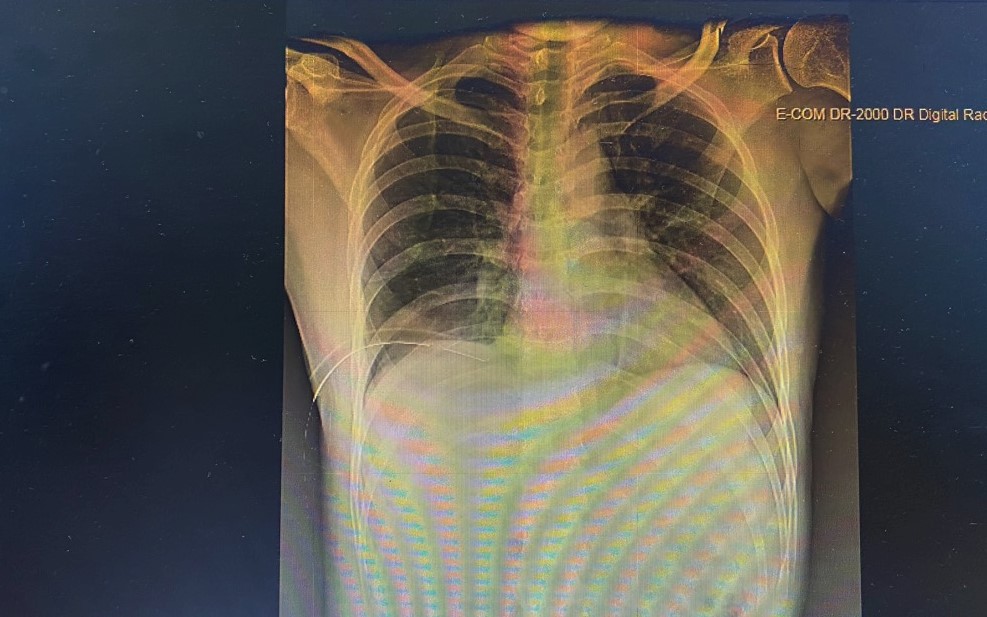

- Bệnh nhân được dẫn lưu màng phổi

Bệnh nhân nhanh chóng được điều trị tích cực theo phác đồ (diệt sán lá phổi, giun đũa chó mèo), dẫn lưu màng phổi, bơm rửa màng phổi hàng ngày, hút khí áp lực âm màng phổi liên tục. Bệnh nhân đáp ứng tốt, hết khí dịch màng phổi, hết ho, không đau ngực, không đau bụng, không sốt. Sau 3 tuần điều trị bệnh nhân ổn định hoàn toàn được ra viện, tiếp tục đơn ngoại trú, hẹn tái khám.